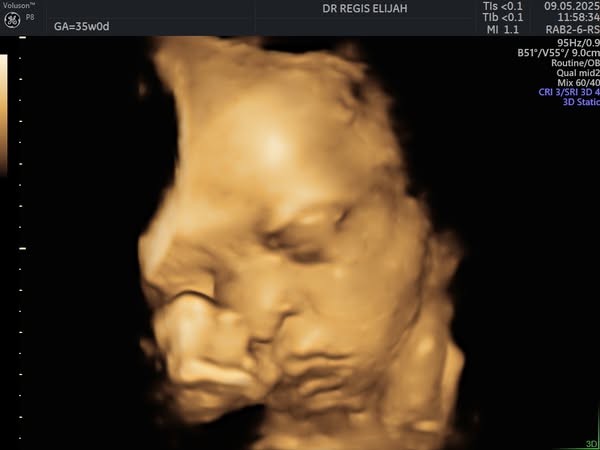

There’s nothing more magical than seeing your baby for the first time—and with our advanced 4D ultrasound technology, you don’t have to wait until delivery day to witness those precious moments!

At Elijah R OBGYN Women’s Clinic, our 4D pregnancy scans allow expectant parents to view their baby’s movements, facial expressions, and little kicks in real time, creating a powerful bonding experience.

🔸 Capture beautiful real-time images

🔸 Detect and monitor fetal development